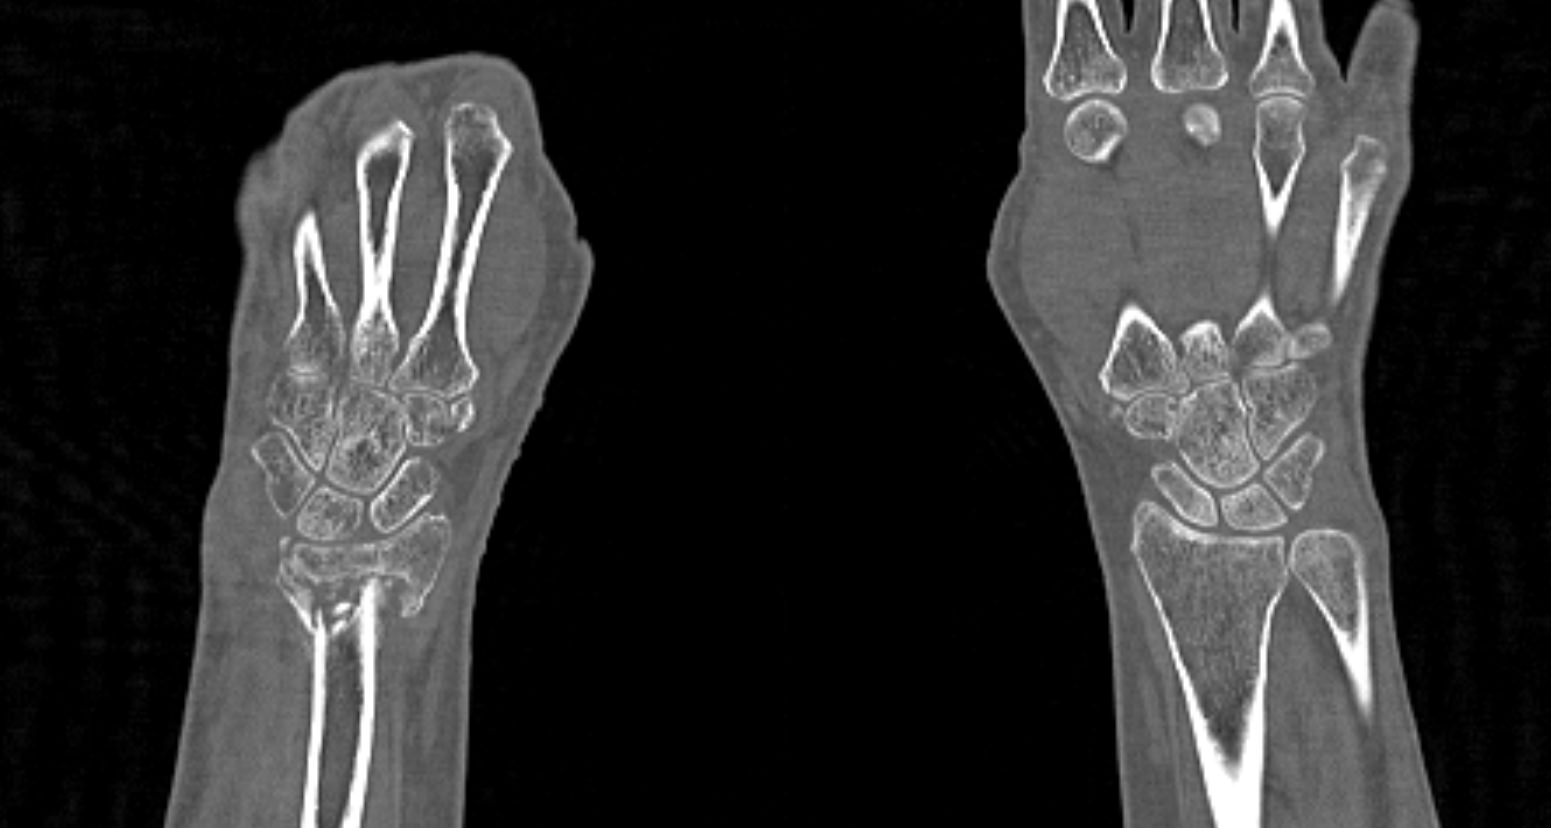

Метод КТ основан на использовании ионизирующего излучения и способности тканей поглощать рентгеновские лучи. Костные ткани обладают высокой плотностью и способны активно поглощать рентгеновские лучи, поэтому они хорошо видны на снимках КТ. В отличие от обычного рентгена компьютерный томограф послойно сканирует исследуемую область в нескольких плоскостях, благодаря чему получаются снимки в мельчайших подробностях. Затем с помощью цифровой обработки данных, полученных при КТ-сканировании, создаются трехмерные модели области исследования.

Таким образом мультиспиральная компьютерная томография позволяет оценить состояние всех структур лучезапястного сустава, выявить травматические повреждения, признаки воспалительных заболеваний, диагностировать аномалии развития и опухолевые образования. При травмах на снимках и трехмерных изображениях хорошо видны фрагменты костных отломков, эти данные используются при подготовке к оперативным вмешательствам. После операции результаты КТ позволяют оценить правильность репозиции костных структур, выявить послеоперационные осложнения, отследить в динамике процесс восстановления тканей.